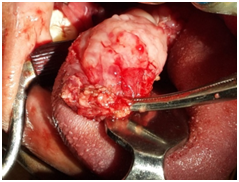

Figure 4 The specimen.

Figure 7 MRI.

Histopathological examination of excised mass was suggestive of histomorphological features suggesting plexiform neurofibroma. The mass consisted of bundles of expanded nerve branches, limited by peripheral rim of eosinophilic membrane. The constituent cells were spindle shaped, with wavy serpentine nuclei. The matrix was composed of fibrocartilagenous tissue with scattered lymphocytic infiltrate.